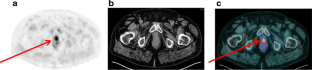

Fig. 1

Fig. 2

Fig. 3

Fig. 4

Fig. 5